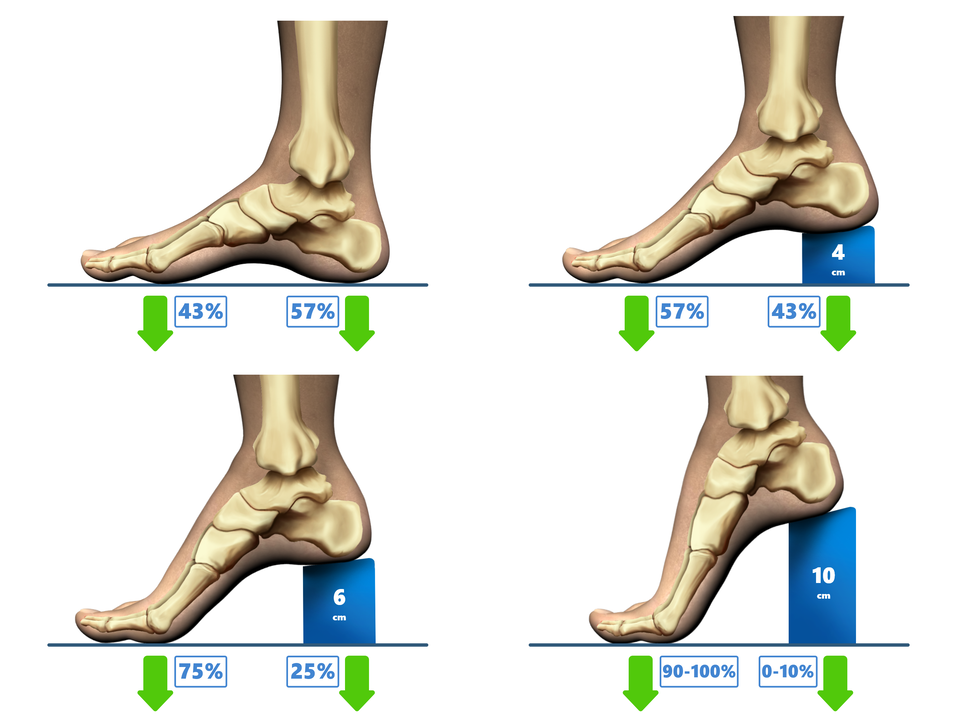

Osią naszego ciała jest kręgosłup, który utrzymuje wyprostowaną postawę. Jego naturalne krzywizny, czyli lordoza szyjna i lędźwiowa oraz kifoza piersiowa i krzyżowa, ułatwiają utrzymanie równowagi przy pionowej postawie ciała. Pełnią także funkcję amortyzatorów podczas chodzenia, biegania, skakania oraz podnoszenia ciężkich przedmiotów. Podobnie prawidłowo ukształtowana, wysklepiona stopa jest przystosowana do przenoszenia dużych i zmiennych ciężarów.

Płaskostopie jest wadą postawy dotyczącą stóp.

Nie dotyka podłoża całą podeszwą, opiera się na nim dwoma punktami śródstopia i piętą., Stopa płaska opis WCAGPrzylega do podłoża prawie całą powierzchnią.

Brak wysklepienia powoduje ból i drętwienie stopy podczas stania i chodzenia.

Wady nabyte są rezultatem długotrwałego utrzymywania ciała w złej pozycji, co powoduje nierównomierne obciążenie mięśni i kości oraz prowadzi do ich osłabienia i deformacji. W przypadku wad kręgosłupa dotyczy to zaburzenia mechaniki mięśni mięśni stabilizujących kręgosłup, natomiast w przypadku płaskostopia mięśni i więzadeł stopy, co skutkuje obniżeniem jej naturalnego wysklepienia.

nieodpowiednie obuwie;

niewłaściwie dobrane buty (wąskie i na wysokich obcasach).